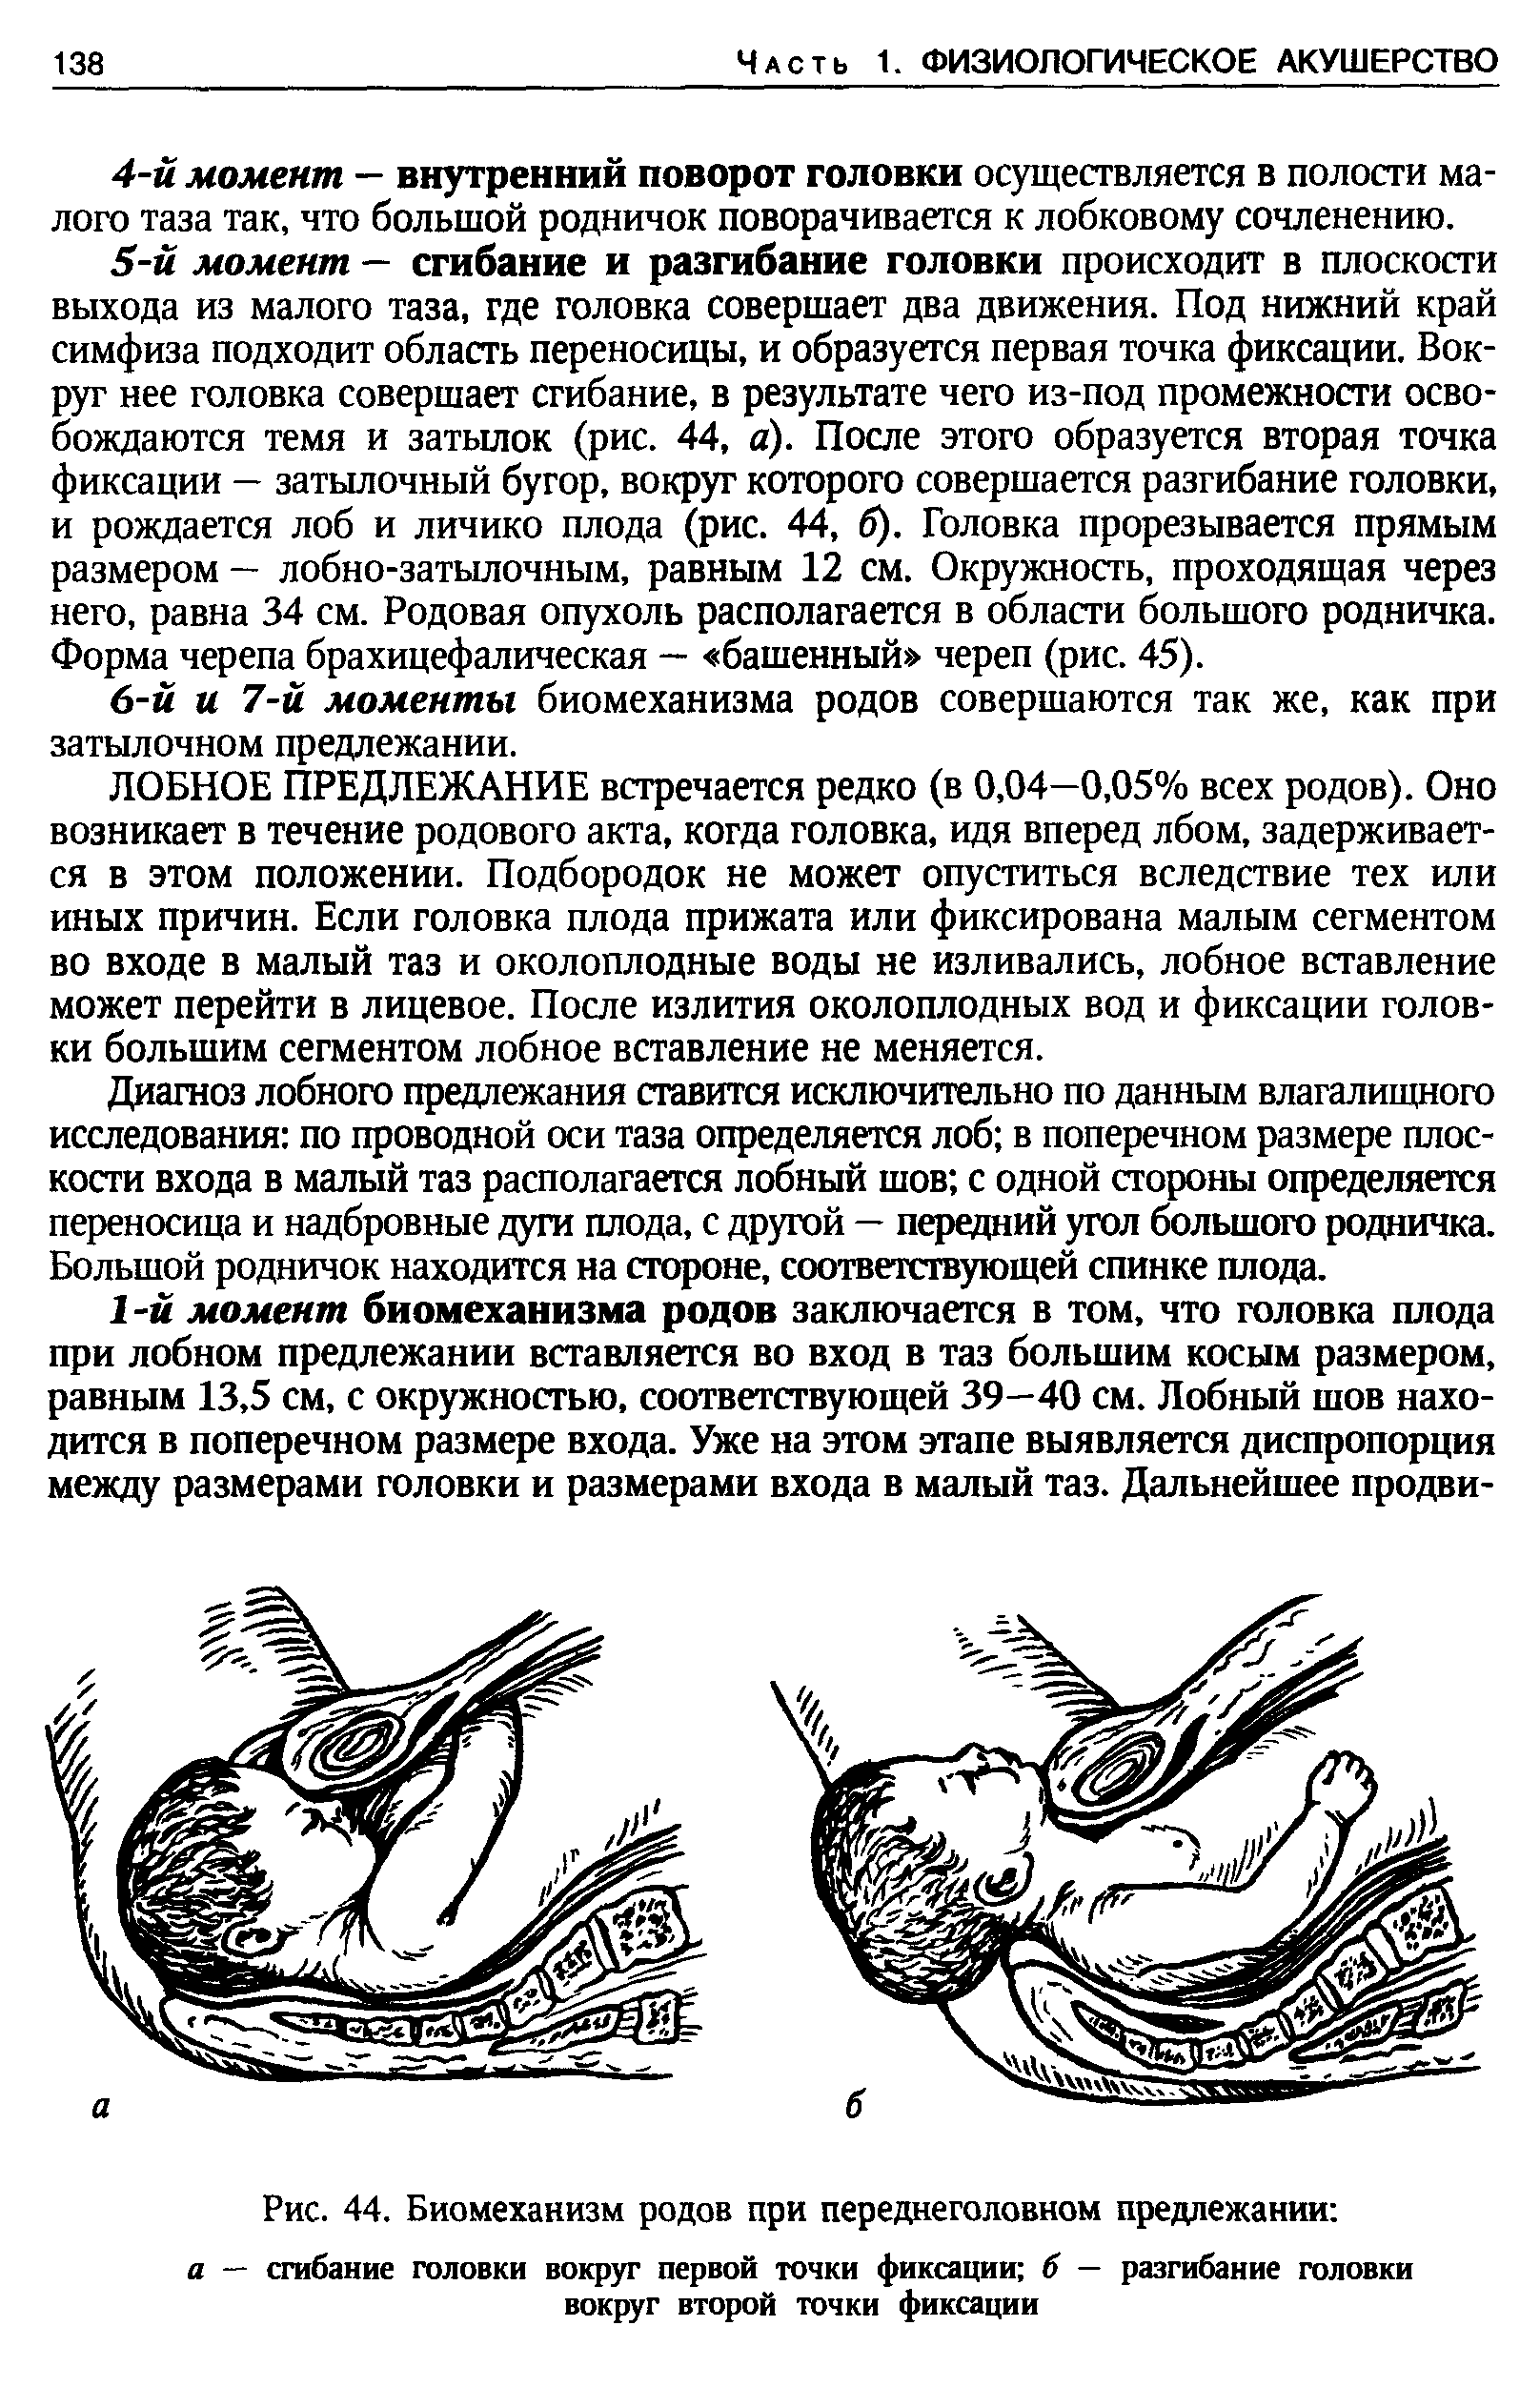

Биомеханизм родов в переднеголовном предлежании

Биомеханизм родов таблица